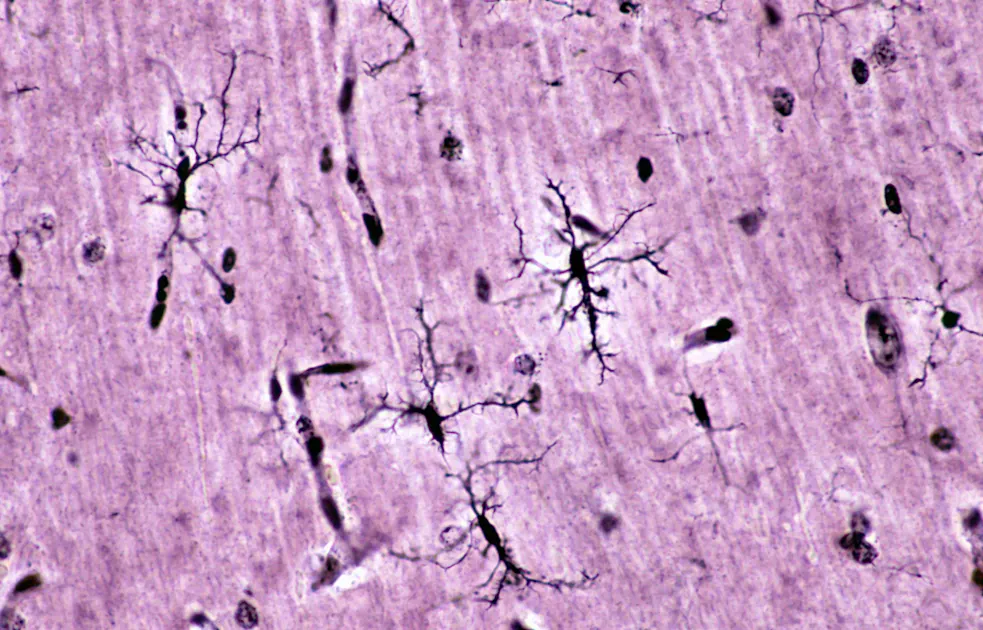

Their findings pointed to microglia—the brain’s resident immune cells (pictured above)—as a key site of activity. This genetic pattern was consistent across developmental stages, from fetal life to adulthood.

“The most important finding in our work is the fact that the genetic risk for type 1 diabetes, is also active in brain cells,” Alagpulinsa says. “This is one of the first studies tying microglia to type 1 diabetes genetic risk.”